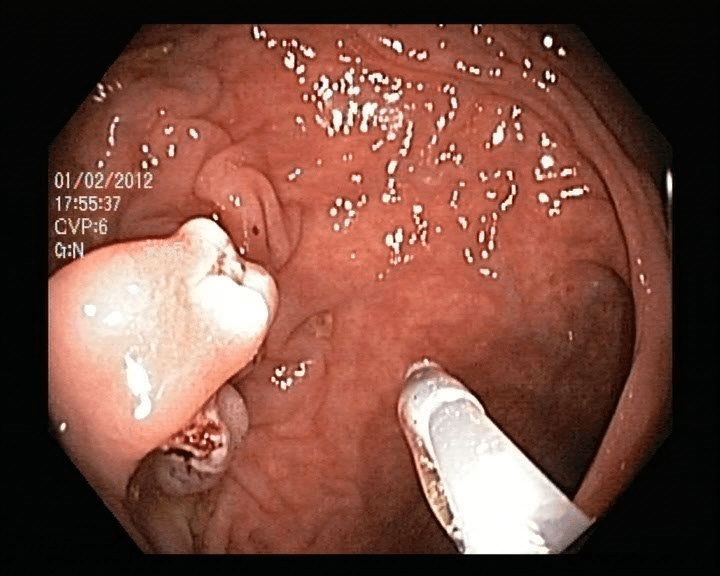

Refer to caption

(a) No abnormality

(b) Polyp

(c) Oesophagitis

(d) Ulcerative Colitis

Figure 1: Illustrations of question-answer pairs along with common abnormalities in gastrointestinal image from ImageCLEFmed-MEDVQA-GI-2023 dataset

The new dataset released for the ImageCLEFmed-MEDVQA-GI-2023 challenge is based on the HyperKvasir dataset [29], the largest gastrointestinal collections with more than 100,000 images, with the additional question-and-answer ground truth developed by medical collaborators. The development set and test set include a total of 3949 images from different procedures such as gastroscopy and colonoscopy, spanning the entire gastrointestinal tract, from mouth to anus. Each image has a total of 18 questions about abnormalities, surgical instruments, normal findings and other artefacts, with multiple answers possible for each, as shown in Table 1. Not all questions will be relevant to the provided image, and the VQA system should be able to handle cases where there is no correct answer. Figure 1 depicts several examples of question-answer pairs on common abnormalities in gastrointestinal tract, such as Colon Polyps, Oesophagitis, and Ulcerative Colitis. As shown in Figure 1(d), there are three possible answers to the question "What color is the abnormality?": "Pink," "Red," and "White", and a typical VQA system should be able to identify all three colors. In general, the image may contains a variety of noise and components that locates across abnormalities, such as highlight spots or instruments, which pose a significant challenge in developing efficient VQA systems for gastrointestinal domain.